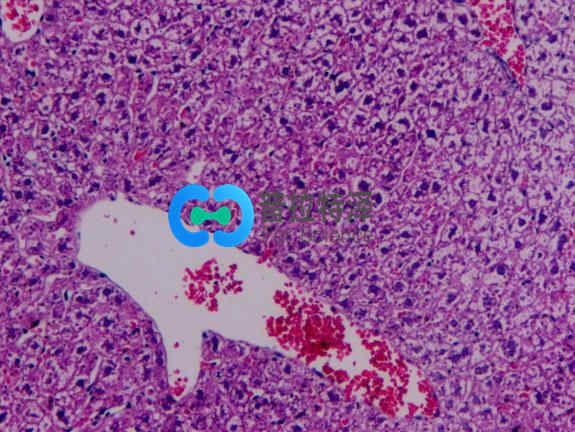

光鏡觀察:

正常組肝小結(jié)構(gòu)正常,肝細胞以中央靜脈為中心呈放射狀排列。無肝細胞腫脹及脂肪變性。模型組肝組織HE染色顯示:造模4周后大鼠肝臟即有輕微的肝細胞脂肪變性,標本還出現(xiàn)匯管區(qū)及小葉內(nèi)炎癥細胞浸潤和散在的點狀壞死;造模8周大鼠多呈中度脂肪變,且炎癥活動積分明顯高于造模4~8 周大鼠,可見到小葉內(nèi)炎癥,炎癥細胞主要以單核細胞為主,炎癥程度明顯加重;造模 18周大鼠呈中重度的大泡性脂肪變,脂滴分布密度通大,可見大部分旺細胞漿含大脂滴,部分脂滴形成大空泡。將細胞核擠壓至一邊,目以中央靜脈周圍為其:肝小葉結(jié)構(gòu)破壞,肝細胞排列不規(guī)救,并伴大量肝細胞腫脹,部分呈氣球樣變,匯管區(qū)炎癥尚輕微。